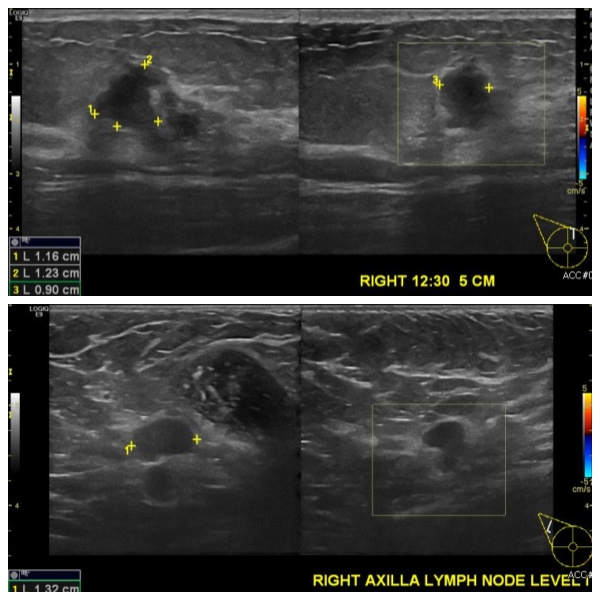

건강검진사 이상 소견으로 내원하신 50대 여성분으로  우측 12:30분 방향에서 5cm 떨어진 거리의 혹 조직검사 시행 하여 우측 침윤성 유관암 진단 되었고, 우측 겨드랑이 림프절 비대 부위 세포검사 시행하여 전이암으로 진단 되었습니다.